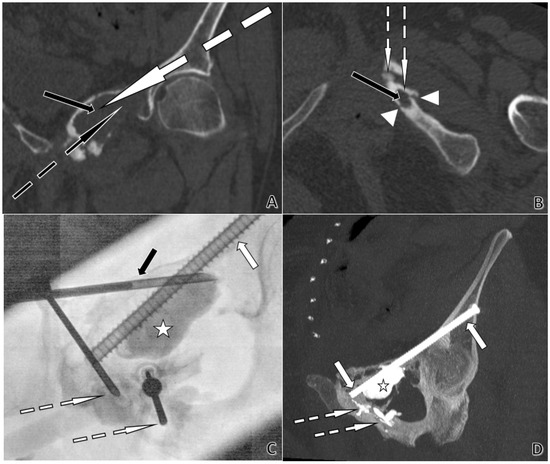

Figure 5.

CT- and fluoroscopy-guided acetabular cementoplasty with screw fixation in a 74-year-old woman. Plasmacytoma extending from the left ischiopubic ramus to the pubic symphysis and the left acetabular roof, with cortical lysis and fractures of the ischiopubic ramus. (A). Coronal CT planning. The black arrow indicates a large lytic lesion of the left iliopubic ramus. The dotted white arrow shows the planned trajectory for an 8-gauge trocar, permitting subsequent placement of a Kirschner-wire and then a 6.5 mm screw from the left iliac wing across the left acetabular roof toward the pubic symphysis. The dotted black arrow marks the planned trajectory for an 11-gauge trocar to cement the large lytic cavity. (B). Axial CT planning. The black arrow shows a lytic lesion of the left ischiopubic ramus. Arrowheads delineate cortical lysis adjacent to the lesion. The dotted white arrows depict short, planned trajectories for two 13-gauge trocars, with only a thin cortex to cross, allowing the use of 13 G instrumentation. (C). Anteroposterior fluoroscopy during cement injection. The white arrow identifies the 6.5 mm anterior-column screw. The dotted white arrows indicate the 13 G trocar positions used for cement injection. The black arrow points to the 11 G trocar. The star marks the large lytic cavity being filled with cement. (D). Post-procedure coronal CT with Maximum Intensity Projection (MIP) at completion. The white arrows show the 6.5 mm screw extending from the left iliac wing across the left acetabular roof toward the pubic symphysis. The dotted white arrow highlights PMMA cement sealing osseous fissures. The star denotes the large lytic cavity filled with cement.